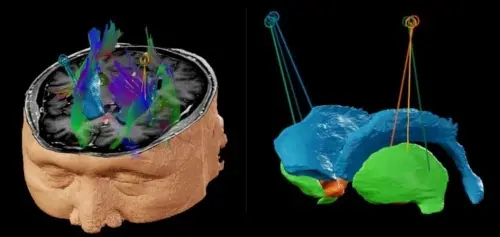

도파민 세포의 뇌이식 수술 모습.

뇌이식 수술 모식도, 뇌 양측 조가비핵(putamen)의 전방, 중간, 후방 부위에 균등하게 이식했다.